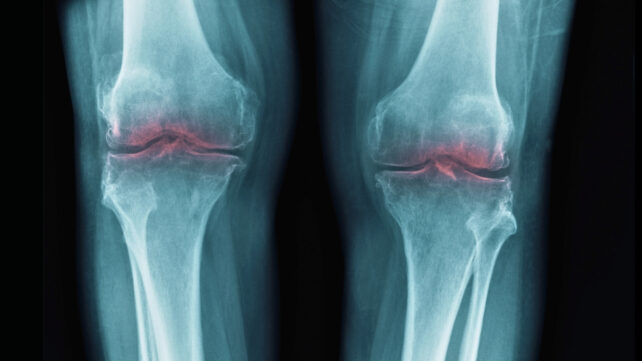

دانشمندان با بررسی دادههای بالینی مختلف متوجه شدند فعالیت منظم بدنی تنها باعث کاهش محدود درد در نواحی لگن، زانو و دست میشود. این میزان تسکین روی یک مقیاس صد امتیازی چیزی بین ۶ تا ۱۲ نمره ارزیابی شده است.

نکته شگفتانگیز این پژوهش هنگام مقایسه فعالیت بدنی با روشهای رایج دارویی برای درمان درد آرتروز مشخص میشود. محققان دریافتند روند تسکین درد با تحرک بدنی درست مشابه مصرف ایبوپروفن یا تزریق مستقیم کورتیکواستروئیدها درون مفصل عمل میکند.